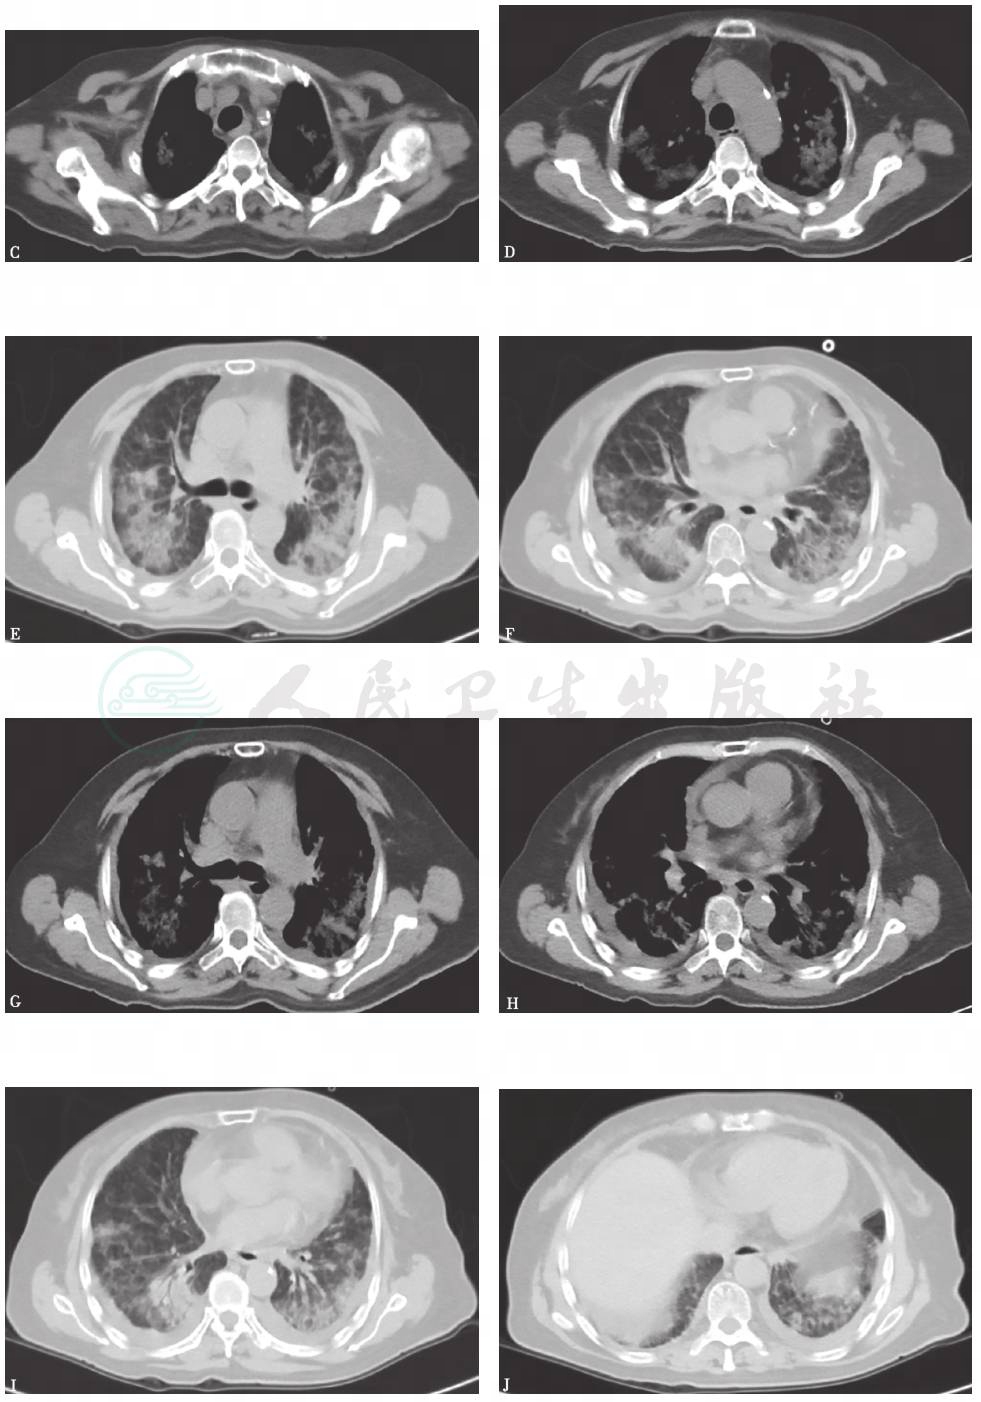

胸部X线检查可见双肺弥漫高密度影,双侧少量胸腔积液(图4),1个月后病灶进一步增多、加重(图5)。胸部CT显示病灶进一步融合增多,伴双侧胸腔积液和心包积液(图6)。

图6 胸部CT表现(2015-06-03)

胸部CT可见双肺多发斑片影、结节影,双侧少量胸腔积液,少许心包积液